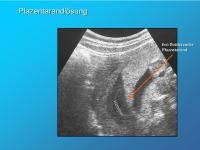

Plazentarandlösung

Abbildung 6

Keywords: BlutungPlazentalösung